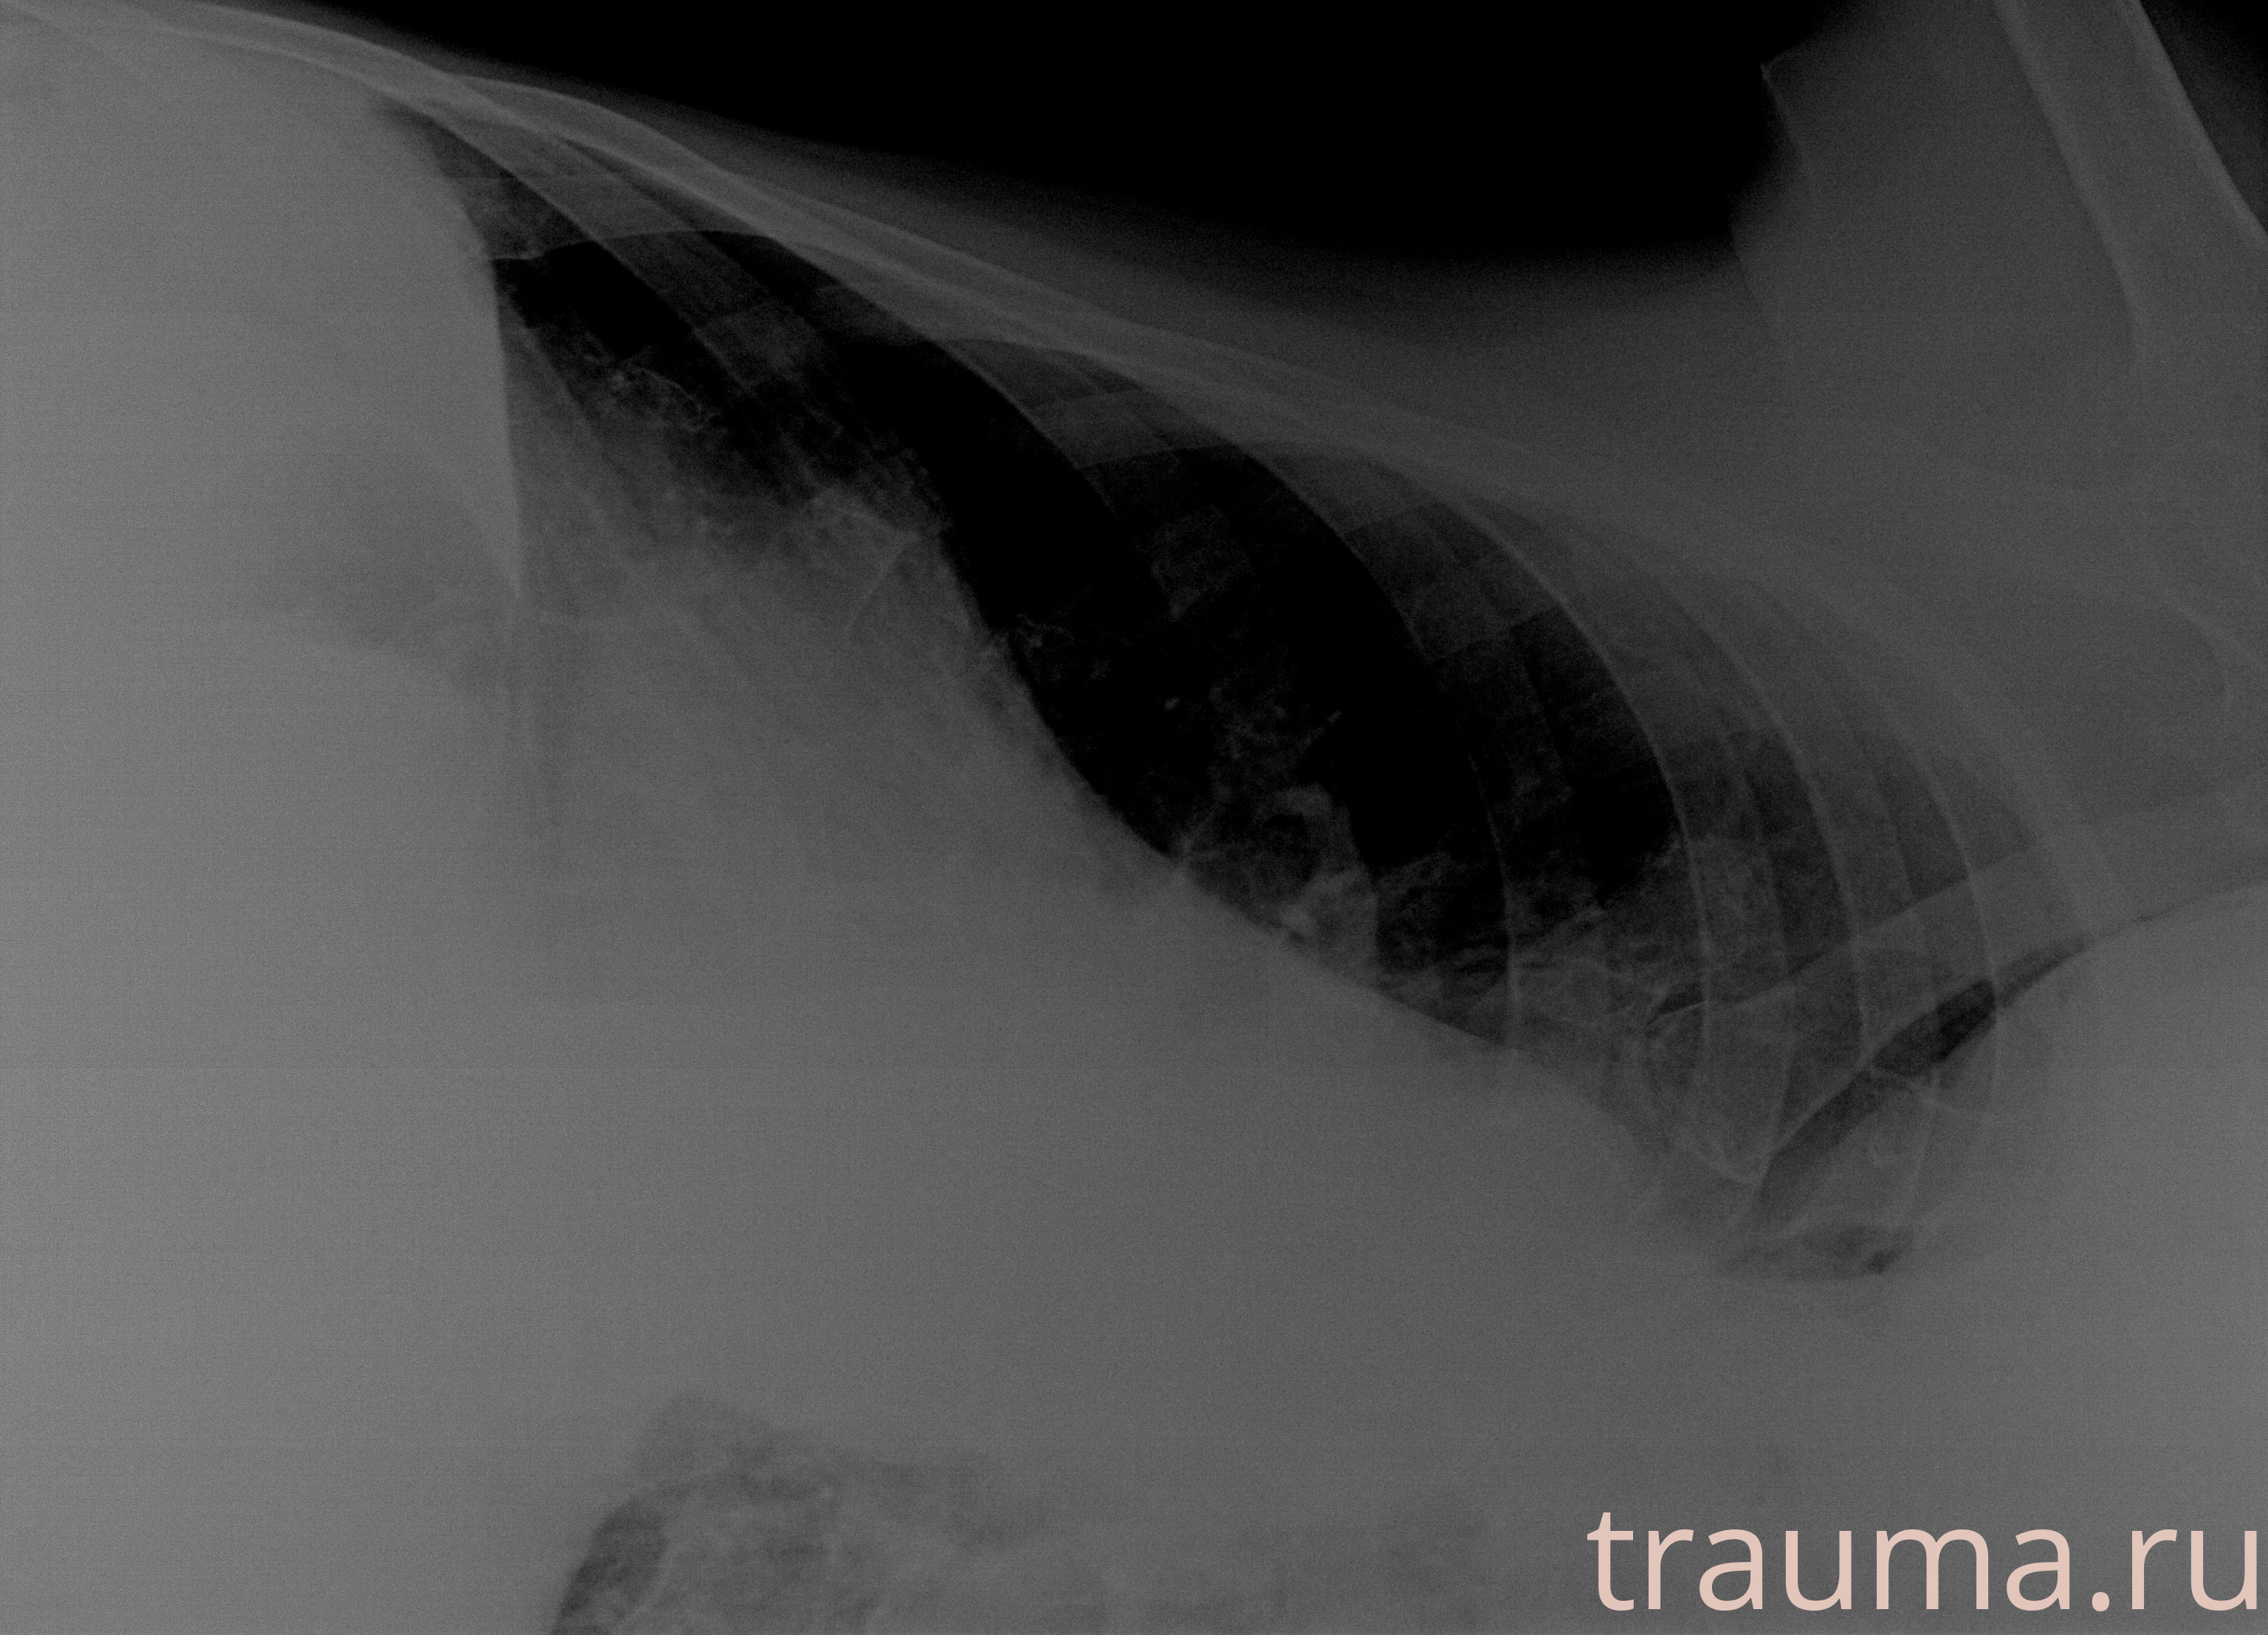

Рентгенограммы

Рентген на дому: по вашему адресу приезжает врач-рентгенолог, травматолог-ортопед с мобильным рентгеновским аппаратом, проводит диагностику травмы или заболевания, делает необходимые рентгенограммы, дает рекомендации по дальнейшему лечению. Получить качественные снимки в домашних условиях возможно благодаря уникальной методике, разработанной МосРентген Центром для института  Склифосовского

Яркость: 1   Контраст: 1   Инвертировать: 0 Увеличение: 1

Перетаскивайте мышь вверх/вниз для контраста, влево/право для яркости. Прокрутка колесом изменяет масштаб. Нажмите Сбросить для возврата к исходному изображению. При увеличении держите мышь в той области, которую хотите рассмотреть.